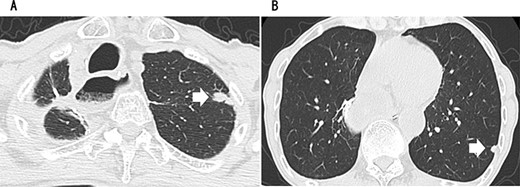

Since no other findings suggestive of distant metastasis were found, partial left lung resection was performed for the two nodules. Both were diagnosed as squamous cell carcinomas (Fig. 4). Furthermore, 5 months after left lung resection, a metastatic liver tumor was found, which was also surgically resected. Finally, 10 years and 4 months after esophagectomy, 3 years after the first lung resection and 1 year after hepatectomy, the patient died due to peritoneal dissemination.

CT revealing a nodule measuring 1.5 cm at the apex of the left lung (A) and a nodule measuring 0.9 cm below the S9 pleura of the left lung (B).